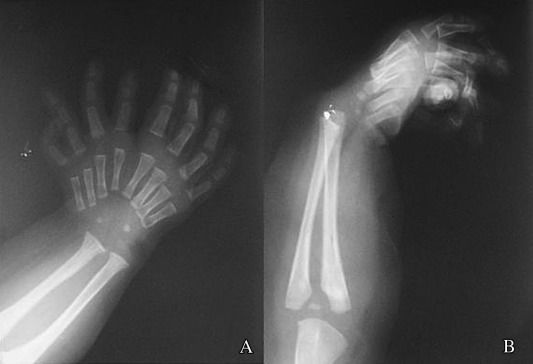

Mirror hand syndrome AKA ulnar dimelia is a rare congenital anomaly of the upper limb. It is characterized by: - duplication of ulna - absence of radius - symmetrical polydactyly Reference: https://www.sciencedirect.com/science/article/abs/pii/S0972978X15000288 Image via: https://www.sciencedirect.com/science/article/abs/pii/S0972978X15000288